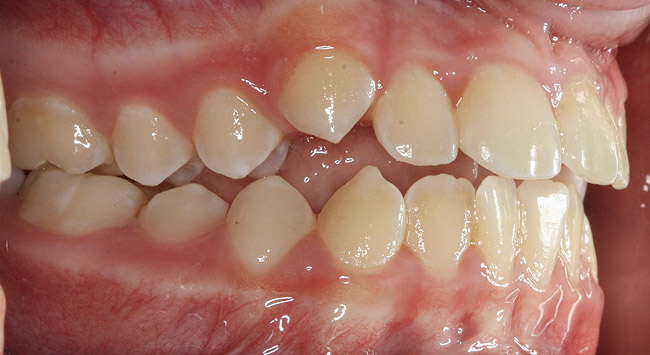

(12.) Class II Angle classification with worn dentition and anterior open bite.

Figure 12